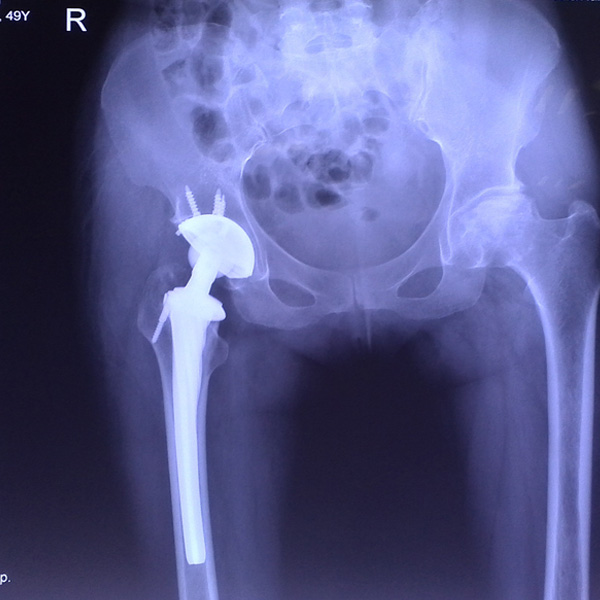

髖關節翻修

患者蘇某,女性,11年前因“左髖關節屈曲攣縮畸形”行左側人工全髖關節置換,近來感覺左髖關節疼痛,不敢行走,經“攜生醫療平臺”就診于哈......